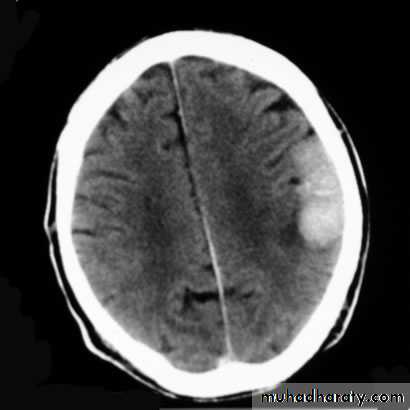

A 60 year old man presents with a seizure. He undergoes a CT brain scan with contrast media.

Your answer

Correct answera.

Left posterior parietal meningioma

b.

Left posterior parietal extradural haematoma

c.

Left posterior parietal astrocytoma

d.

Left posterior parietal subdural haematoma

What is the most likely diagnosis?

a : Left posterior parietal meningiomaThere is a uniformly enhancing, extra-axial mass lesion measuring 5 cm x 2.5 cm in diameter in the left posterior parietal region. It contains some curvilinear calcification. There is little associated oedema but no midline shift. This is a left posterior parietal meningioma.

b : Left posterior parietal extradural haematoma

This is a left posterior parietal meningioma.

c : Left posterior parietal astrocytoma

d : Left posterior parietal subdural haematoma